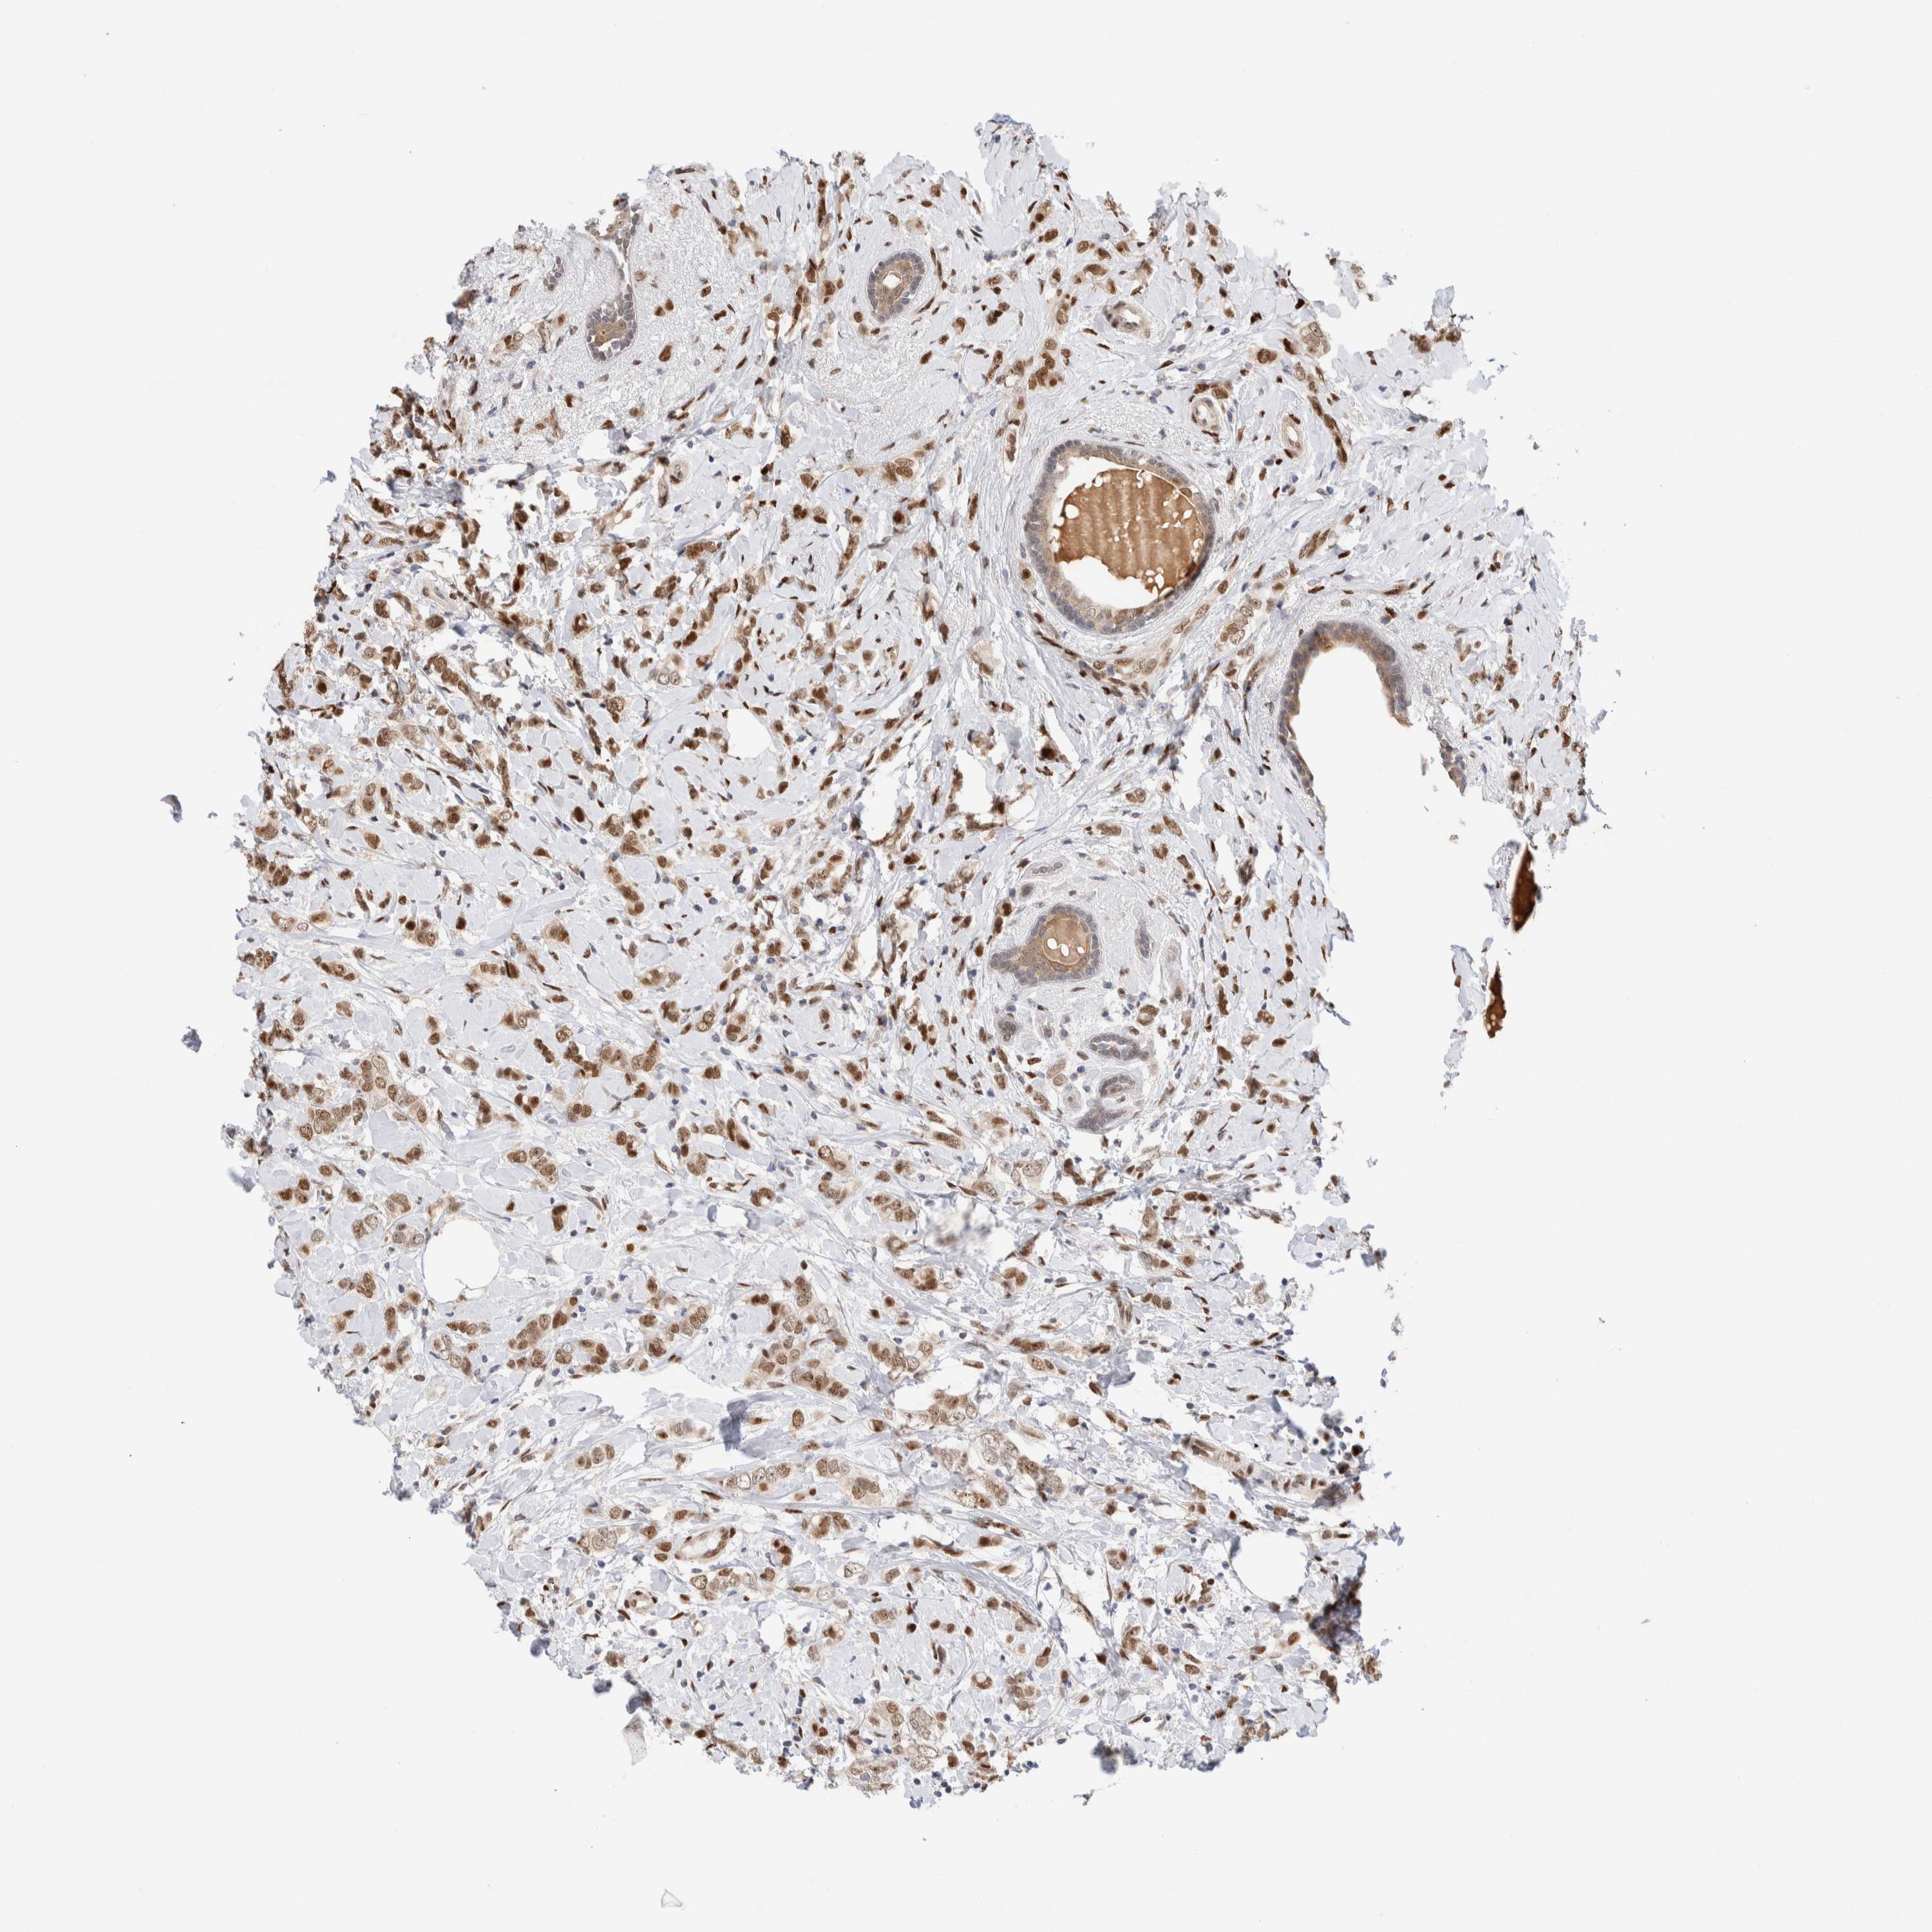

CANCER BREAST CANCER Show tissue menu

BRCA TCGA BRCA VALIDATION PROTEIN EXPRESSION